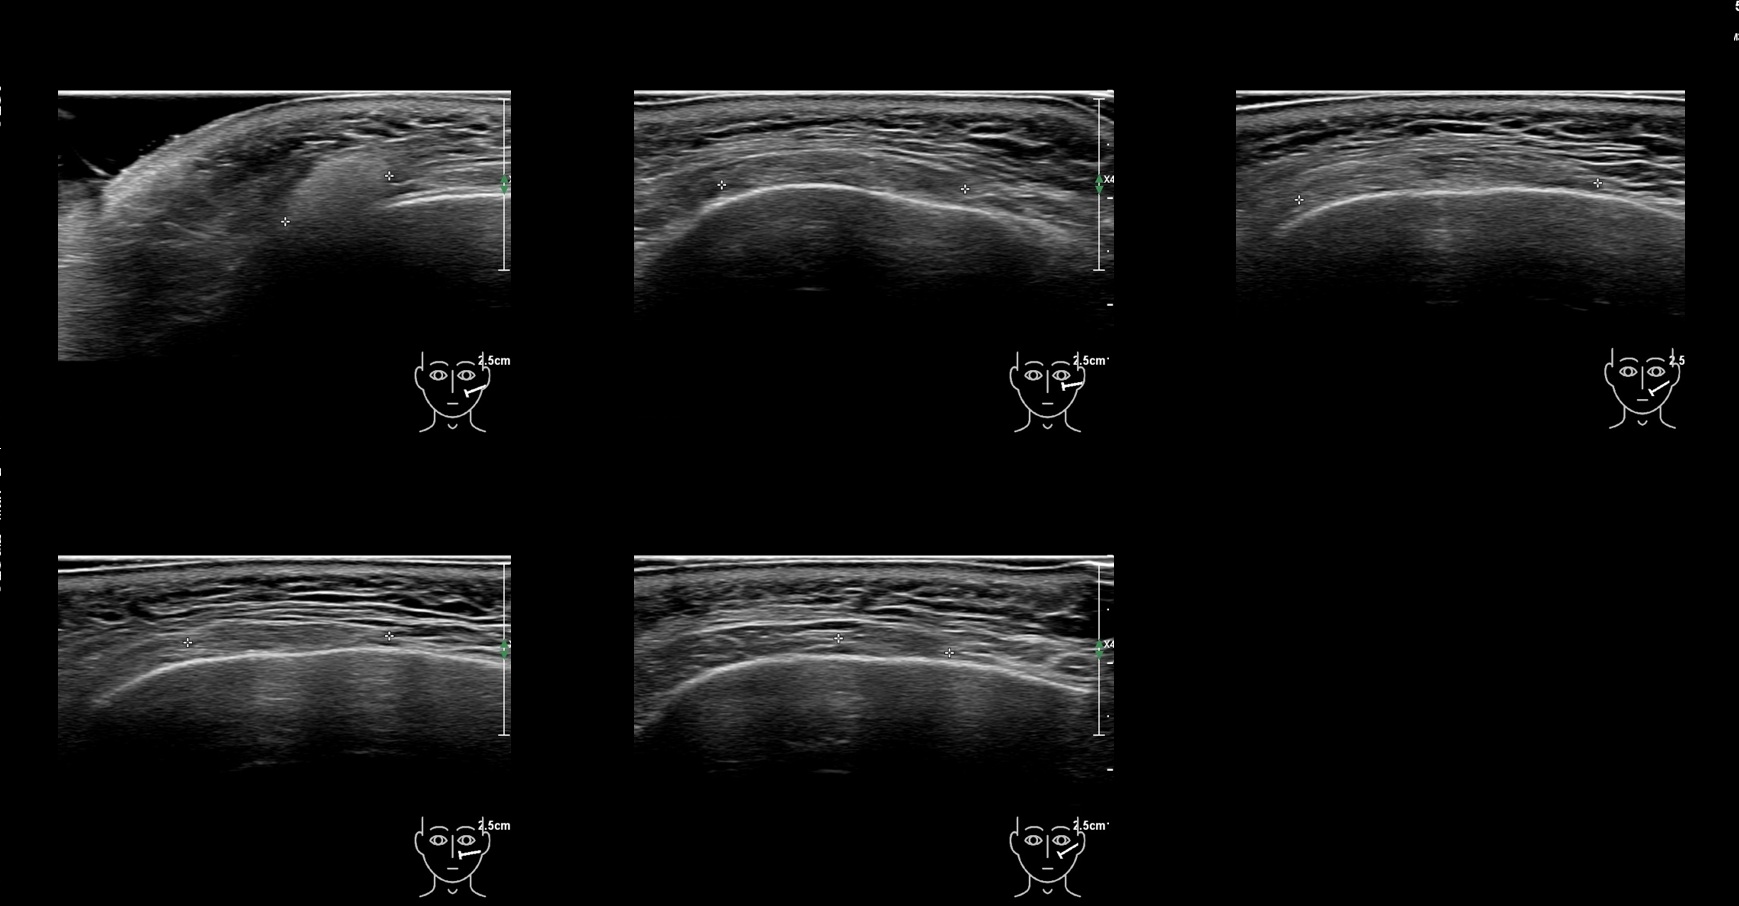

Draw in the image on the right where the fillers are located. To check if your answer is correct, please click on the secondary image.

Draw in the second image below where the fillers are located. To check if your answer is correct, swipe the first image to the right.